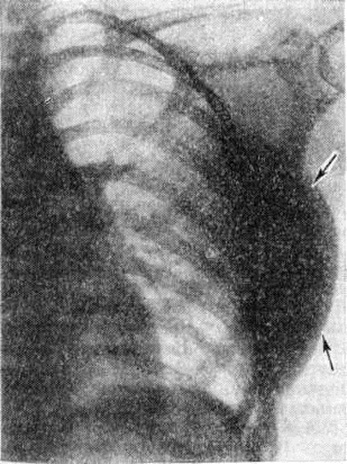

Рис. 2.

Рентгенограмма левой половины грудной клетки с липомой мягких тканей грудной стенки (прямая проекция): видна большая полуовальная тень опухоли с чёткими границами (указана стрелками).

На рентгенограммах Липома представляет гладко-очерченное просветление обычно правильной формы. Просветление, образуемое Липома, как правило, гомогенное, но изредка в нем встречаются мелкие участки обызвествления. Форма просветления зависит от плотности органов, между которыми заключена Липома Подкожная узловатая Липома проявляется в виде чётко очерченного округлой формы образования, интенсивность тени которого одинакова с окружающей жировой тканью (рисунок 2). Большие, длительно существующие Липома вызывают смещение окружающих тканей.